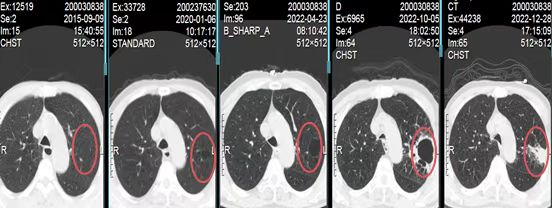

患者近8年反复因慢阻肺急性加重住院,期间多次行肺部CT(如下图)。

从上图可以看出,2015年开始患者持续随访肺部CT,2015年左肺可见“肺大疱”(不明显),2020年开始出现肺大疱样改变,随着随访时间的延长,肺大疱逐渐增大,且肺大疱周围可见肺组织实变影,外院多次行肺部CT考虑感染性空洞,那究竟这个在8年时间不断变化的“肺大疱”究竟是什么?

有趣的是,囊腔型肺癌的影像表现并非一成不变,在动态随访过程中, 病灶形态可以呈现不同改变。研究发现,随着肿瘤生长,囊腔可逐渐消失、闭塞,形成实性肿块[3-4],例如本例患者。目前也有研究认为形成的机制在支气管末端形成一个“活瓣”,使得空气易进难出,这可以解释许多囊腔随着时间发展而增大。